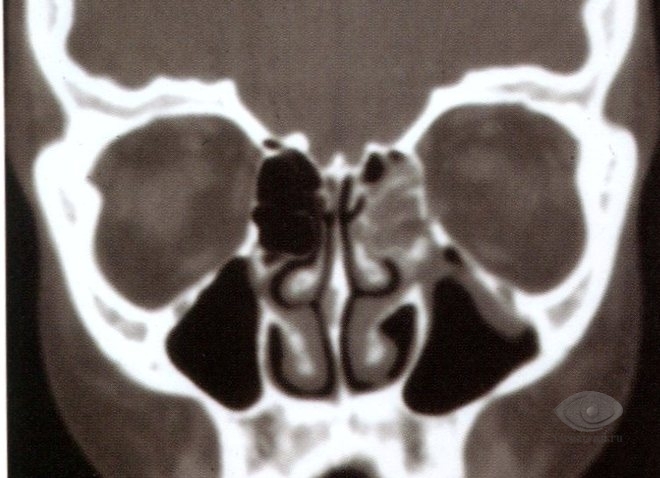

Каждая стенка имеет свои особенности. Наружная стенка самая прочная, внутренняя может повреждаться при незначительных травмах. Верхняя, внутренняя и нижняя стенки содержат воздушные пазухи: лобную сверху, решетчатый лабиринт внутри и гайморовую снизу. Это соседство может приводить к распространению воспалительных процессов из пазух в глазницу. Глазница соединена с полостью черепа через отверстия и щели, что увеличивает риск распространения воспаления в мозг.

Внутренняя стенка глазницы является наиболее хрупкой стенкой глазницы, которая повреждается даже при тупых травмах, за счет чего, практически всегда, в ткани века или самой глазницы поступает воздух — развивается, так называемая, эмфизема. Она проявляется увеличением тканей в объеме, а при ощупывании определяется мягкость тканей с появлением характерного хруста – перемещения воздуха под пальцами. При воспалительных процессах в области решетчатой пазухи, они могут достаточно легко распространяться в полость глазницы с выраженным воспалительным процессом, при этом, если формируется ограниченный гнойник, он называется абсцессом, а распространенный гнойный процесс – флегмоной. Воспаления в глазнице могут распространяться в сторону головного мозга, а значит являться опасными для жизни.

Нижняя стенка образована, в основном, верхней челюстью. От заднего края нижней стенки начинается подглазничная борозда, продолжаясь далее в подглазничный канал. Нижняя стенка глазницы является верхней стенкой гайморовой пазухи. Переломы нижней стенки достаточно часто возникают при травмах, сопровождаясь опущением глазного яблока и ущемлением нижней косой мышцы с ограничением подвижности глаза кверху и кнаружи. При воспалении или опухолях, располагающихся в пазухе верхней челюсти, они также достаточно легко переходят в глазницу.

- Рентгенография, компьютерная томография и магнитно-резонансная томография для выявления нарушений целостности костных стенок глазницы, наличия инородных тел, воспалительных процессов и опухолей.